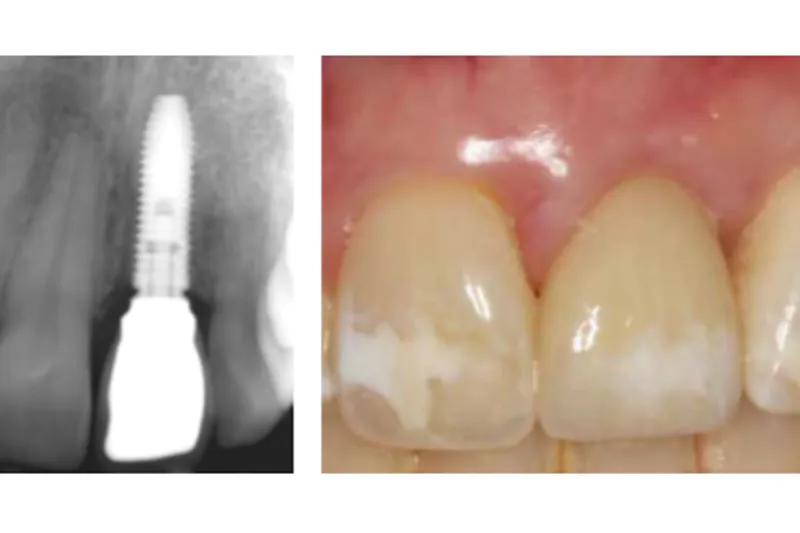

a556 fig. 6

Desuden tyder det også på, at bevarelse af en endodontisk behandlet tand i forhold til ekstraktion og indsættelse af et implantat i det mindste på kort sigt resulterede i den bedste blødtvævsæstetik.